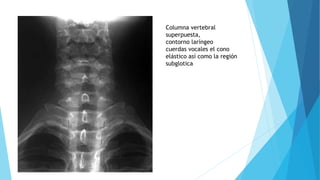

Columna vertebral

superpuesta,

contorno laríngeo

cuerdas vocales el cono

elástico así como la región

subglotica